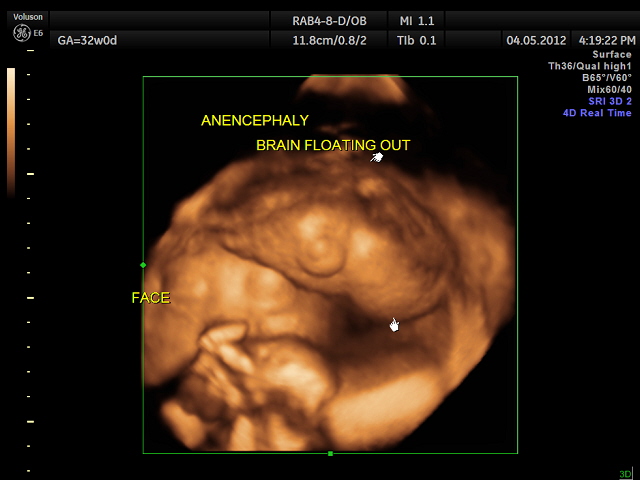

Anencephaly: 32 weeks Gestation Date: May 20, 2012Author: kriznan Category: Fetal Ultrasound Tags: 32 weeks gestation, anencephaly, calvarium, fetal brain, fetal ultrasound Post navigation NON IMMUNE HYDROPS → The image demonstrates a case of anencephaly: the calvarium (roof of the skull) is absent, and the images shows the brain floating out. Unfortunately, this was detected at 32 weeks gestation. Share this: Share on X (Opens in new window) X Share on Facebook (Opens in new window) Facebook Email a link to a friend (Opens in new window) Email Share on LinkedIn (Opens in new window) LinkedIn Share on WhatsApp (Opens in new window) WhatsApp More Print (Opens in new window) Print Share on Reddit (Opens in new window) Reddit Share on Tumblr (Opens in new window) Tumblr Share on Pinterest (Opens in new window) Pinterest Share on Telegram (Opens in new window) Telegram Like Loading...